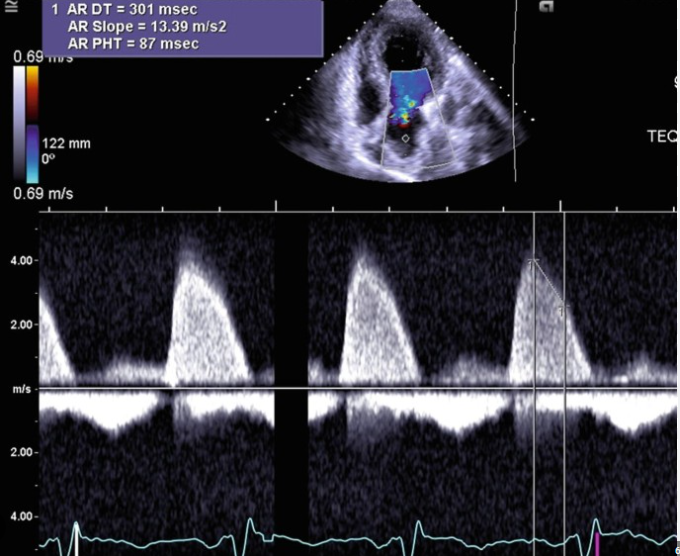

Pressure Half-Time by Continuous-Wave Doppler

AoV

o To assess aortic insufficiency severity

o Apical four-chamber or apical long axis view (three-chamber view)

o Obtain complete Doppler spectral waveform (3 – 5 meters per second)

o If velocity is low – probably not getting complete waveform

o Obtain pressure half-time on complete waveforms only

o Mild (flat) = greater than 500 milliseconds

o Severe (steep) = less than 200 milliseconds

o Assess the density of the spectral Doppler signal

• Pressure half-time greater than 500 milliseconds

• Pressure half-time less than 200 milliseconds

AI PHT

AO PHT (ms)

mild

moderate

severe

mild

>500 ms

moderate

500 - 350 ms

350 - 200 ms

severe

< 200 ms